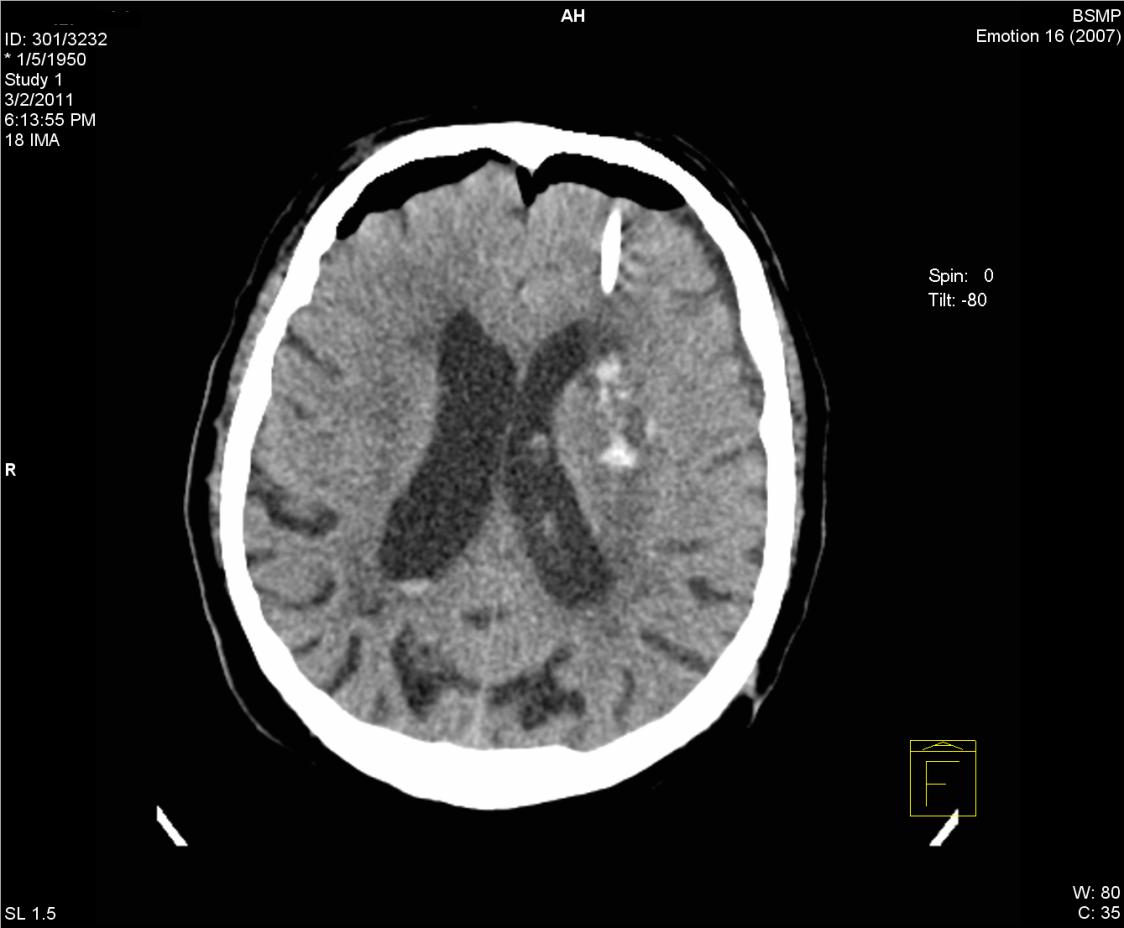

Нейрохирургами проведены две операции по удаление опухолей головного мозга. Навигационная система определила точное месторасположение опухоли и нейрохирург оптимизировал подход к патологическому очагу с минимальными повреждениями. Также проведена одна операция по удалению внутримозговой гематомы с помощью эндоскопического тубуса. При таком кровоизлиянии операционный подход сопровождается разрушением большой зоны мозговой ткани. При использовании навигации операция проводится через 1,5 сантиметровой туннель.